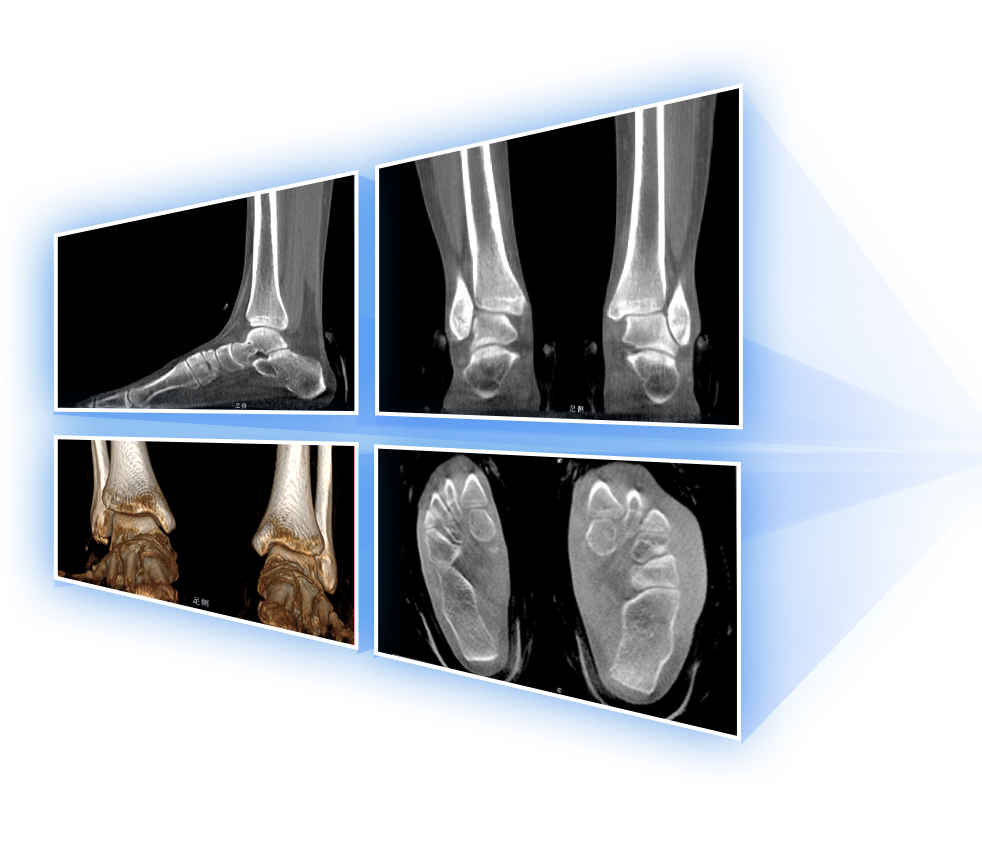

· 補位CT,提供負重位三維影像

· 引領普放走向三維精準診斷時代

填補常規CT/MR空白

助力術前規劃和術后評估

足踝

精準診斷

手術方案規劃

術后隨訪

VR體繪制重建